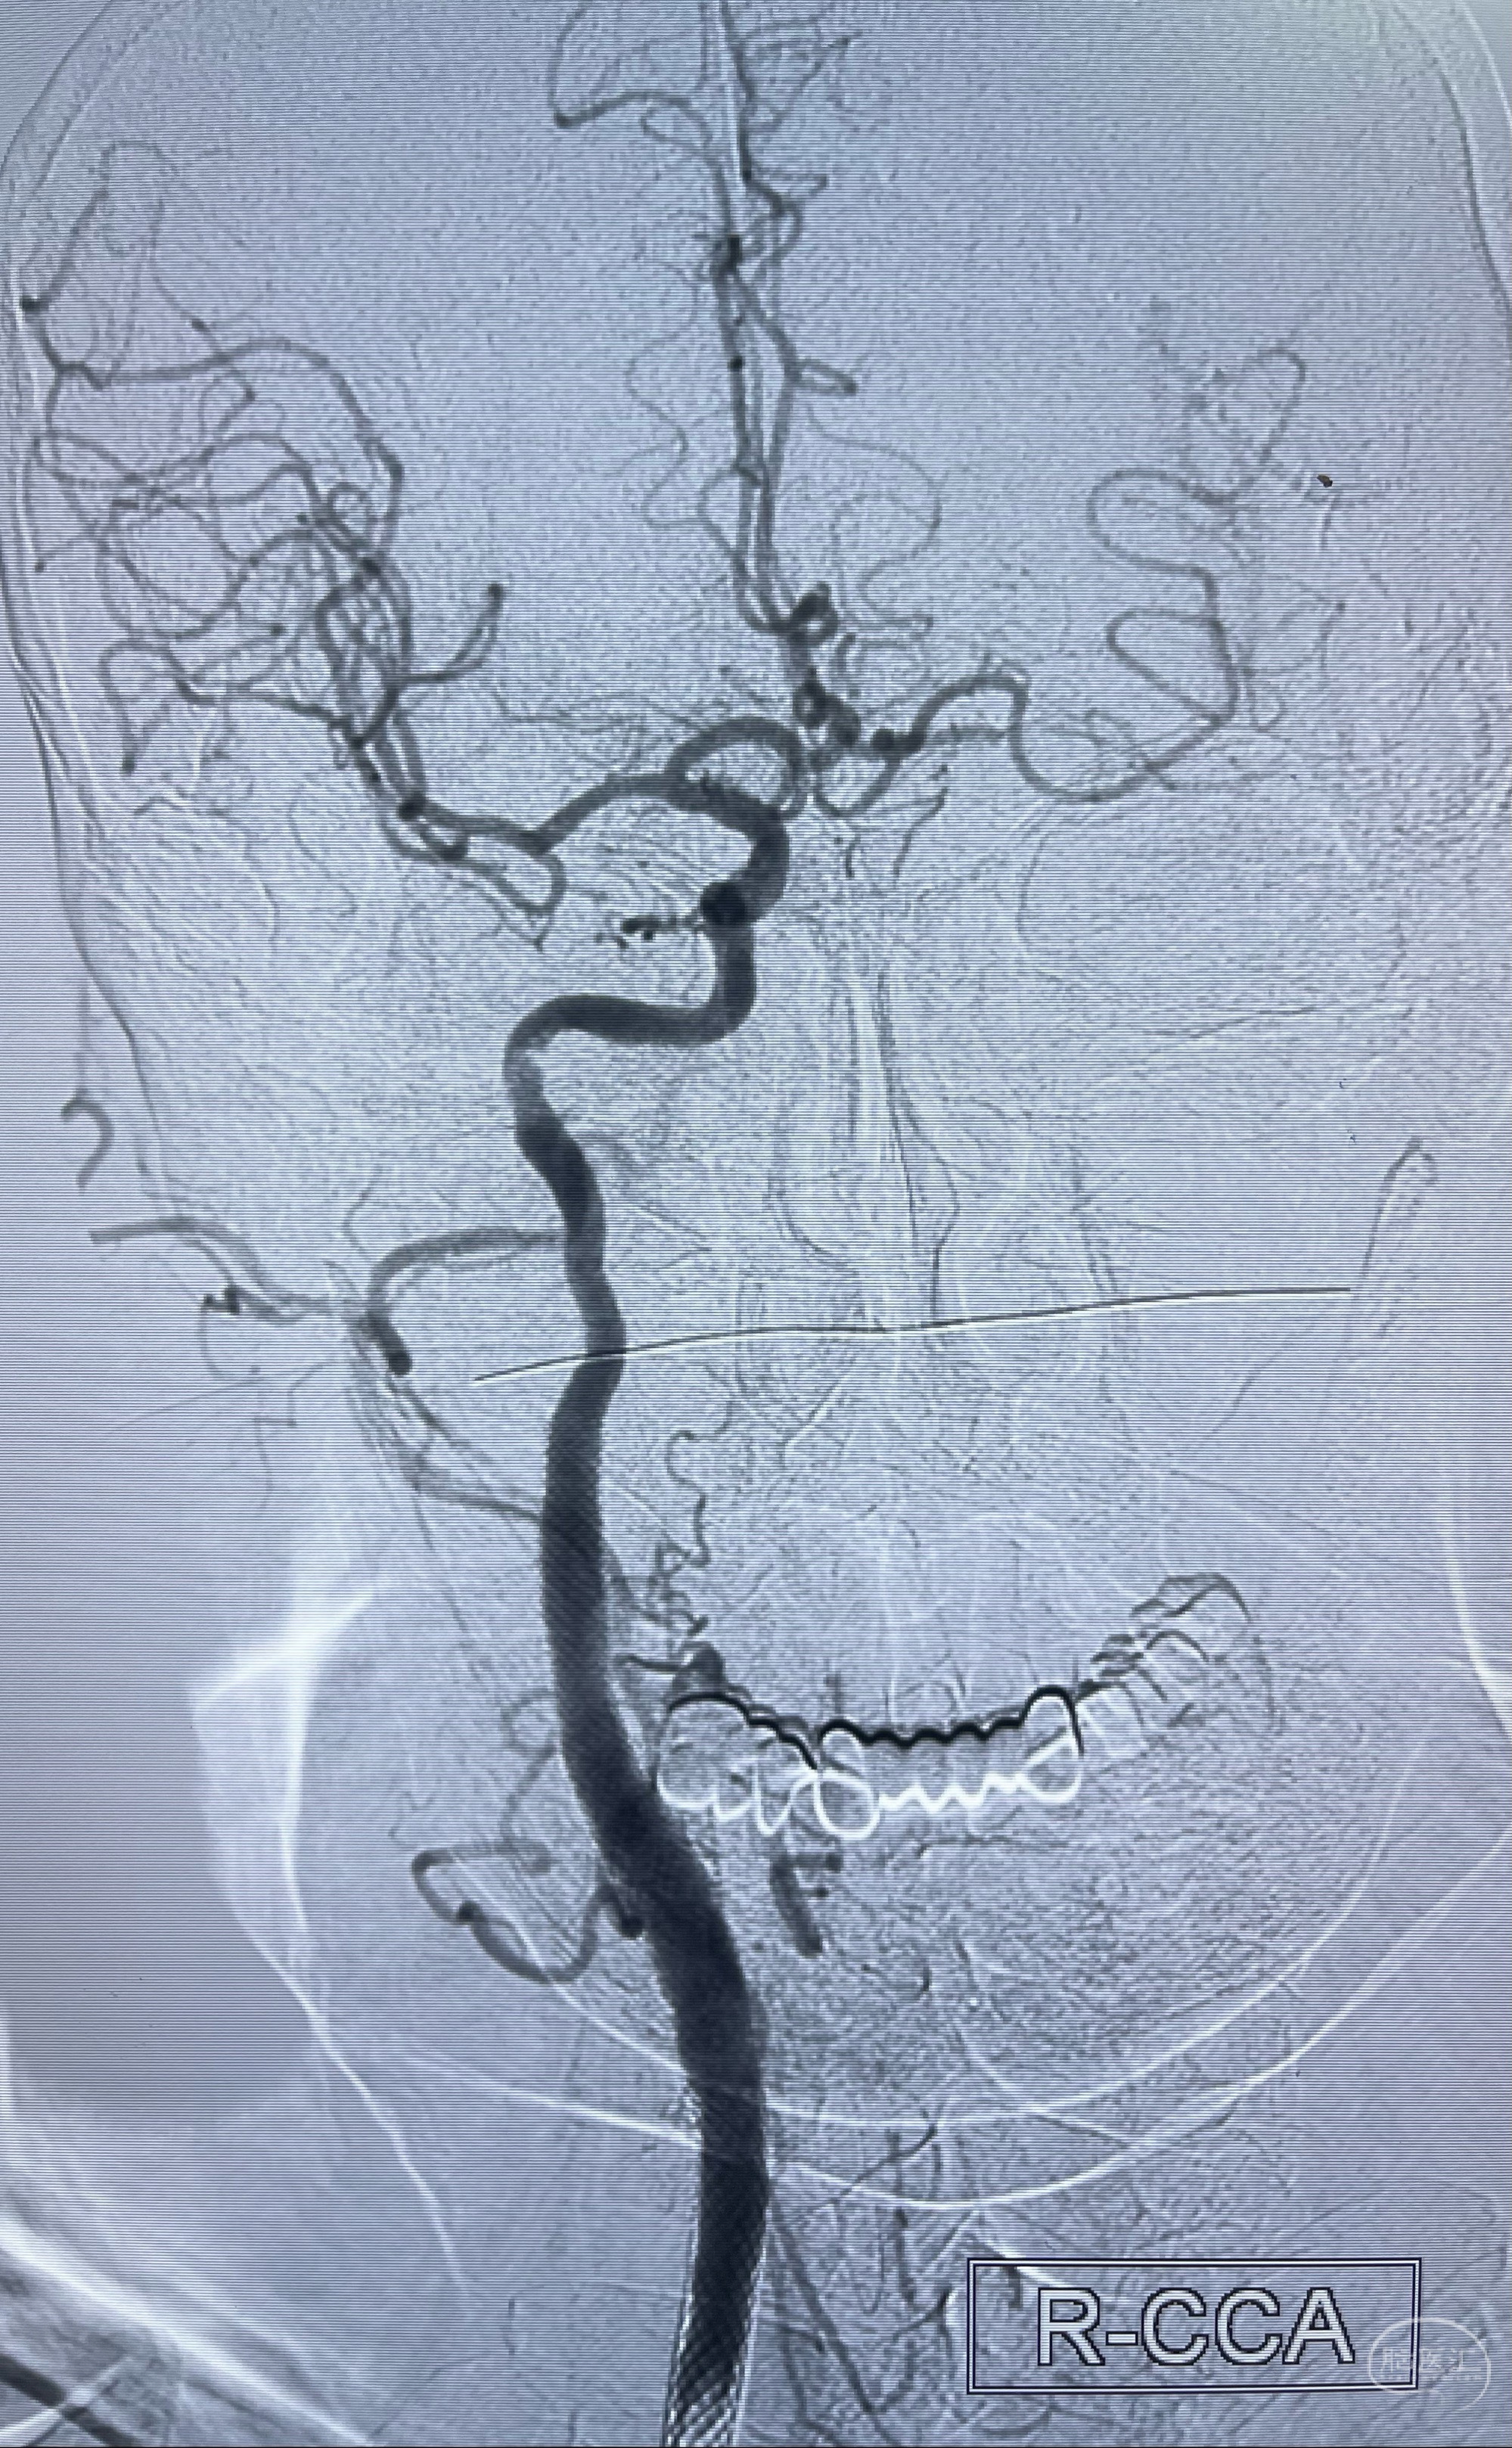

2023-07-10DSA:右侧颈内动脉岩骨段夹层伴中偏重度狭窄改变,左侧颈总动脉闭塞、右侧颈外动脉由右侧肋颈干甲颈干吻合代偿

箭头所示为颈内动脉岩骨段重度狭窄,结合MRI,考虑为肿瘤侵犯右侧颈内动脉

箭头以近至支架段管腔不规则狭窄

经导引导管造影显示支架远端颈内动脉不规则狭窄伴局部充盈缺损,同时行全身肝素化5ml

重新行“路径图”,支架导管在微导丝引导下超选择性插入至右侧颈内动脉眼段,4.5-50mmLeo支架释放,远心端位于海绵窦段,近心端位于岩骨段狭窄段以近

即刻造影显示支架贴壁佳